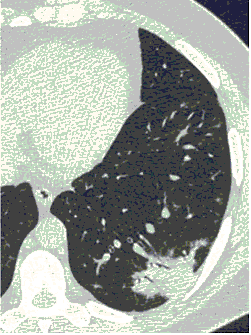

2. Наличие клинических проявлений, указанных в п. 1, в сочетании с характерными изменениями в легких по данным компьютерной томографии (КТ) (см. Приложение 1 настоящих рекомендаций) вне зависимости от результатов однократного лабораторного исследования на наличие РНК SARS-CoV-2 и эпидемиологического анамнеза.

- Изменения при КТ (рентгенографии), типичные для вирусного поражения (объем поражения минимальный или средний; КТ 1-2)

- Изменения в легких при КТ (рентгенографии), типичные для вирусного поражения (объем поражения значительный или субтотальный; КТ 3-4)

- Изменения в легких при КТ (рентгенографии), типичные для вирусного поражения критической степени (объем поражения значительный или субтотальный; КТ 4) или картина ОРДС.

КТ имеет высокую чувствительность в выявлении изменений в легких, характерных для COVID-19. Применение КТ целесообразно для первичной оценки состояния ОГК у пациентов с тяжелыми прогрессирующими формами заболевания, а также для дифференциальной диагностики выявленных изменений и оценки динамики процесса. КТ позволяет выявить характерные изменения в легких у пациентов с COVID-19 еще до появления положительных лабораторных тестов на инфекцию с помощью МАНК. В то же время, КТ выявляет изменения легких у значительного числа пациентов с бессимптомной и легкой формами заболевания, которым не требуется госпитализация. Результаты КТ в этих случаях не влияют на тактику лечения и прогноз заболевания при наличии лабораторного подтверждения COVID-19. Поэтому массовое применение КТ для скрининга асимптомных и легких форм болезни не рекомендуется.